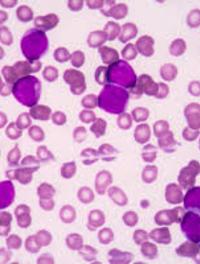

Les taux de guérison des enfants, adolescents et jeunes adultes atteints de leucémie lymphoblastique aiguë (LLA) se sont beaucoup améliorés [...]

L’incidence de la leucémie aiguë myéloïde (LAM) augmente avec l’âge avec un âge médian au diagnostic d’environ 70 ans. Le pronostic [...]

Tisagenlecleucel est un traitement par cellules T porteuses d’un récepteur antigénique chimérique (CAR) qui cible le CD19. Ce traitement [...]